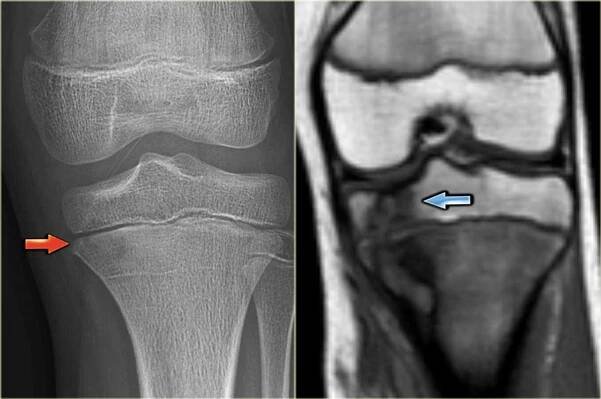

osteoidní osteom, benigní kostní nádor.

rtg a mri, mrt, ct s výraznou sklerózou v okolí ložiska. koncept lékařské léčby. diagnostika onemocnění lidských kostí. - nárt - stock snímky, obrázky a fotky

Osteoidní osteom je benigní nádor projevující se noční bolestivostí, která příznivě reaguje na acylpyrin. Vyskytuje se v koriové části kosti, kde edémem kolem sebe působí bolesti okostice.